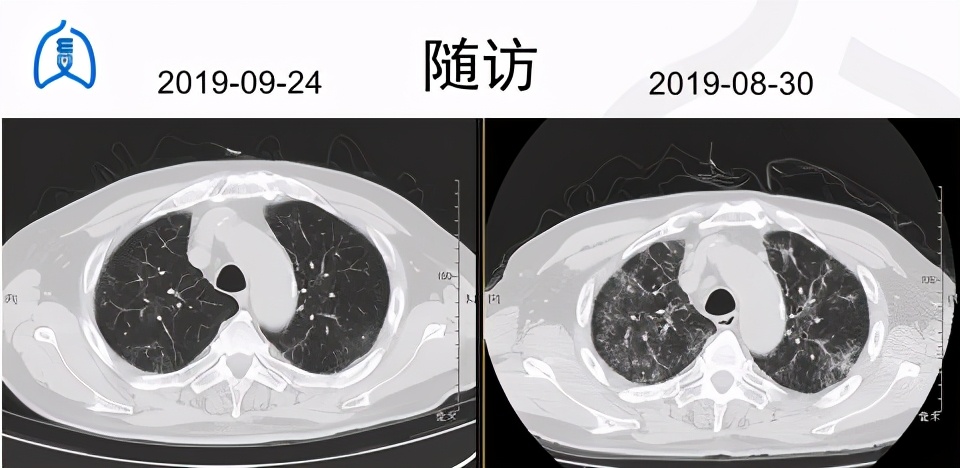

9月7日起,停用胺碘酮,用索塔洛尔控制心律失常;用甲强龙40mg ivgtt qd、阿奇霉素0.5g ivgtt qd、富露施控制肺间质疾病;行补钙、保护胃黏膜等治疗。

患者于2019年9月24日到我院随访,活动后气促的症状已得到明显改善,胸部CT示双肺间质性炎症灶较前也有明显好转,查动脉血气示PaO2:81mmHg,PaCO2:38mmHg,相较于9月2日的PaO2:65-68mmHg有明显提升。